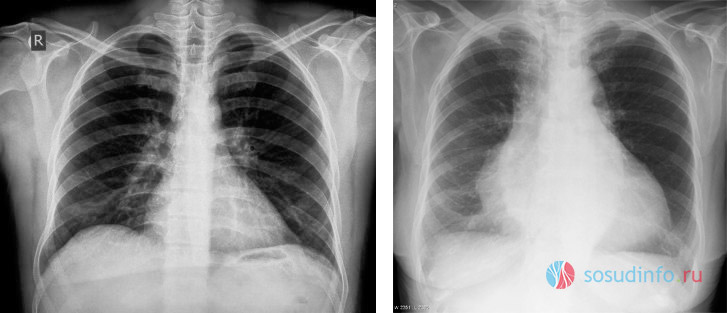

В дополнение к эхокардиоскопии применяются рентгенография органов грудной клетки, электрокардиограмма, МРТ сердца и пункционная биопсия сердечных тканей (в случае подозрения на опухоль сердца, что происходит крайне редко).

Симптомы этого врожденного заболевания достаточно характерны: у новорожденного сразу после рождения могут наблюдаться цианоз лица или всего тела, одышка при плаче и сосании, а также выраженная тахикардия. Для подтверждения диагноза у новорожденных применяются рентгенография грудной клетки и УЗИ сердца.